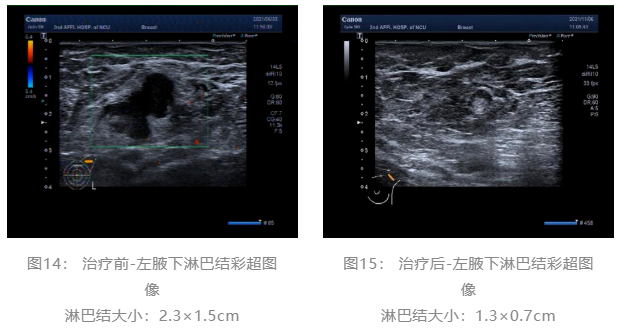

▌治疗前后影像学对比:

术前评估:新辅助治疗期间患者无明显不适,一般状况可。新辅助治疗后左乳房肿瘤及腋下肿大淋巴结退缩明显,疗效评估PR,未发生不良事件,择期可行左乳癌改良根治术。

随着靶向药物的研究进展,越来越多的的研究开始探索在不影响患者预后的前提下,是否可以避免使用蒽环类化疗药物。KRISTINE研究8结果证明,TCbHP方案在新辅助治疗中的有效性和安全性;Ⅱ期TRYPHAENA研究9结果也提示,在曲妥珠单抗联合帕妥珠单抗双靶治疗的前提下,使用以紫杉和卡铂为基础化疗的pCR结果与紫杉和蒽环为基础的化疗相当;TRAIN-2研究10对比了FEC-TCbHP和TCbHP方案在HER2阳性早期乳腺癌中的疗效,结果显示两组的疗效终点没有显著性差异,两组pCR分别为67%和68%,但是使用蒽环类化疗的患者出现了更高比例的发热性中性粒细胞减少(10% vs 1%)和心脏毒性事件(8.6% vs 3.2%)。目前对于HER2阳性乳腺癌的新辅助治疗,2022.V2版NCCN指南11也不再将含蒽环类方案作为首选的推荐。在此病例中,患者选择了THP方案进行新辅助治疗,在治疗6个周期后,影像学评估为PR,术后病理提示患者达到了pCR,再次证实该方案的有效性。